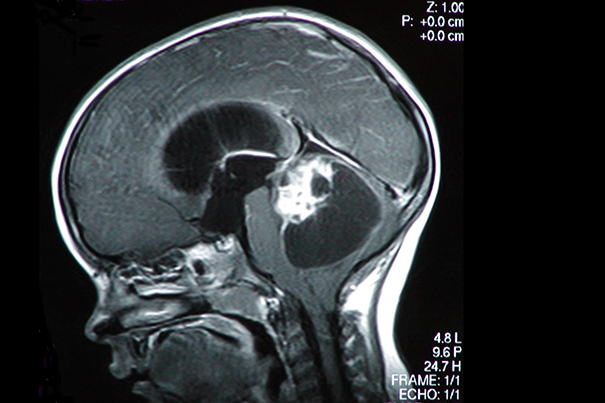

A new study shows that advances in pediatric brain cancer may be turning a corner thanks to precision medicine. “Although there has been a great deal of progress over the past 30 years in improving survival rates for children with cancer, advances in pediatric brain cancer (pictured) haven’t been as dramatic,” says co-lead author Pratiti Bandopadhayay of Dana-Farber/Boston Children’s.

“Although there has been a great deal of progress over the past 30 years in improving survival rates for children with cancer, advances in pediatric brain cancer haven’t been as dramatic,” says co-lead author Pratiti Bandopadhayay of Dana-Farber/Boston Children’s, who is also an instructor in pediatrics at Harvard Medical School (HMS).

“In a recent study, brain tumors accounted for 25 percent of all pediatric deaths attributed to cancer. In addition, many of the current therapies can result in long-term difficulties in cognitive or physical functioning,” adds Bandopadhayay.